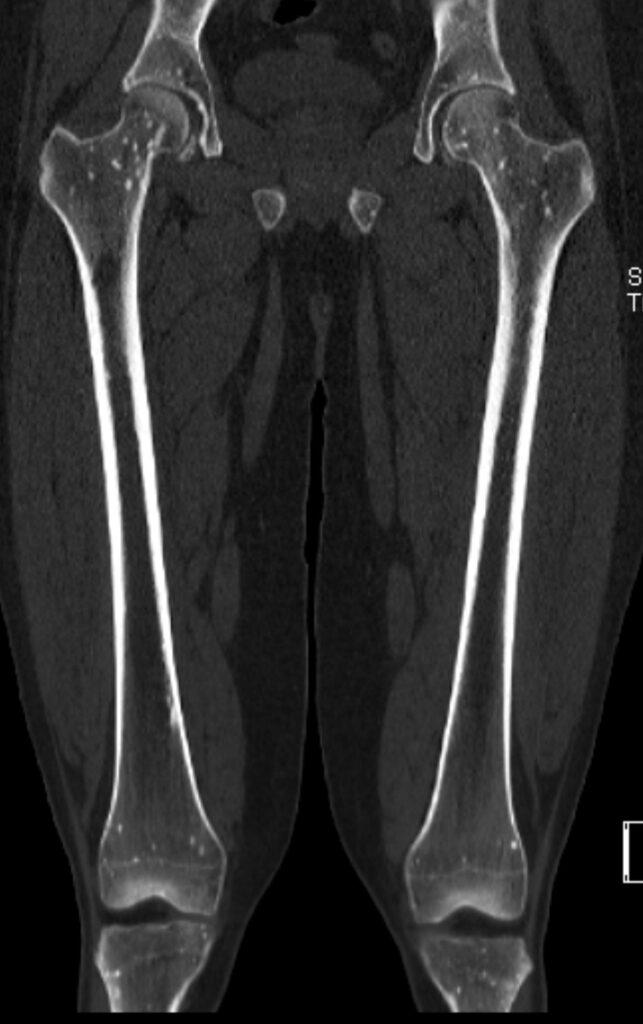

*31-year-old male presented with hip pain.

What is the most likely diagnosis?

Osteopoikilosis

CT images revealed the bone islands of osteopoikilosis, typically clustered around joints.

The bone islands of osteopoikilosis are typically clustered around joints and align themselves parallel to surrounding trabeculae. Most lesions are found in the appendicular skeleton and pelvis. The axial skeleton is largely spared. The lesions vary in size, usually a 5-10 mm, but ranging from only 1-2 mm up to 1-2 cm.